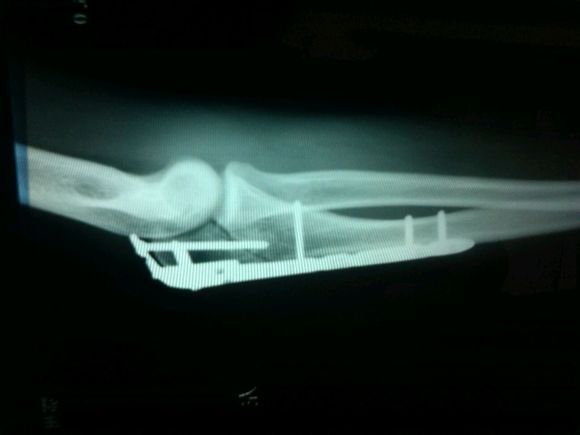

左尺骨鹰嘴骨折,现在已经八个月来,胳膊还伸不直,活动还是没原来灵敏 该怎么办,取钢板得过多久啊? 点击展开 匿名用户 2014-04-17 12:26 为您推荐: 其他回答 病情分析: 你的片子上好像还有骨缝? 指导意见: 没有长好一般是不能拿掉钢板的。 有钢板“保护”,长好后可以“努力”锻炼。不用害怕。 等骨头长好就可以考虑拿掉钢板了。 匿名用户 2014-04-17 14:25 相关问题 左肘尺骨鹰嘴骨折手术钢板固定已六十天能同房吗 尺骨鹰嘴粉碎性骨折手术后怎样恢复手臂 医生:您好,我儿子19岁尺骨及尺骨鹰嘴骨折,手